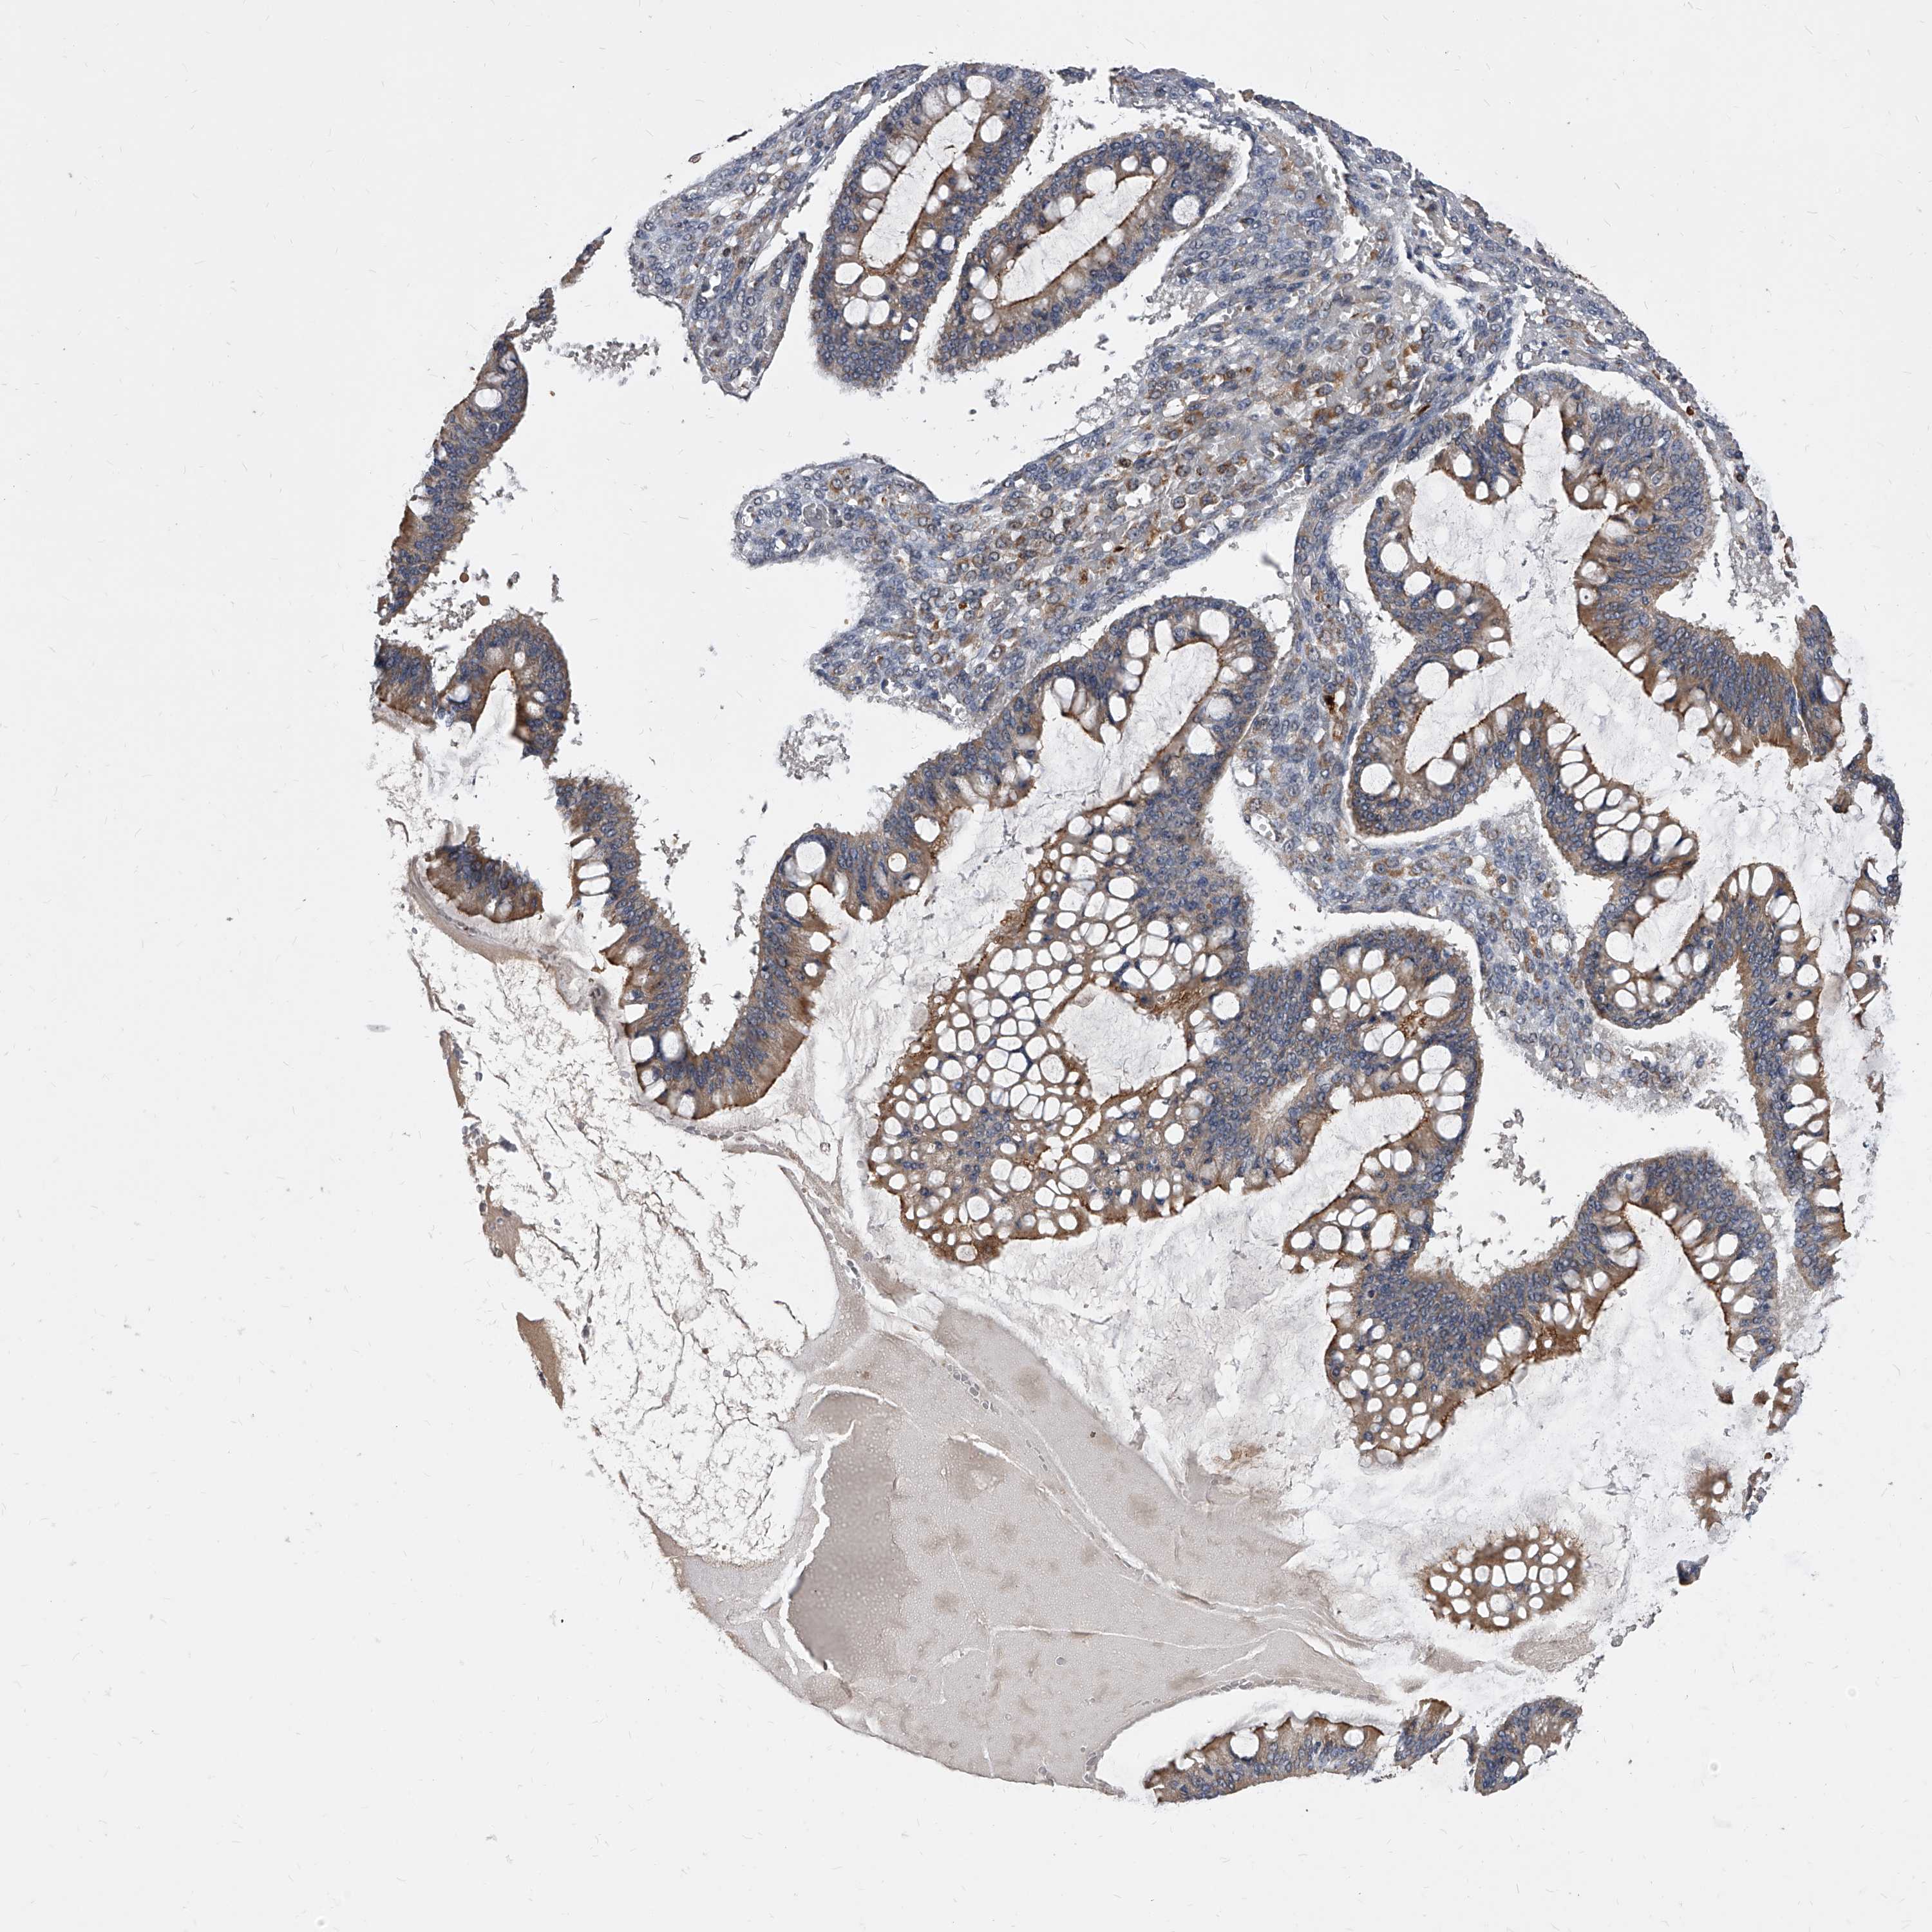

OVARIAN CANCER - Protein expressioni

A mouse-over function shows sample information and annotation data. Click on an image to view it in a full screen mode. Samples can be filtered based on level of antibody staining by selecting one or several of the following categories: high, medium, low and not detected. The assay and annotation is described here.

Note that samples used for immunohistochemistry by the Human Protein Atlas do not correspond to samples in the TCGA dataset.

Antibody stainingi

Antibody staining in the annotated cell types in the current human tissue is reported as not detected, low, medium, or high, based on conventional immunohistochemistry profiling in selected tissues. This score is based on the combination of the staining intensity and fraction of stained cells.

Each image is clickable and will lead to virtual microscopy that enables deeper exploration of all samples and also displays staining intensity scores, fraction scores and subcellular localization as well as patient and tissue information for each sample.

Antibody HPA029242

Staining

High

Medium

Low

Not detected

Intensity

Strong

Moderate

Weak

Negative

Quantity

>75%

75%-25%

<25%

None

Location

Nuclear

Cytoplasmic/membranous

Cytoplasmic/membranous,nuclear

Cystadenocarcinoma, serous, NOS

Carcinoma, endometroid

Cystadenocarcinoma, mucinous, NOS

Carcinoma, NOS